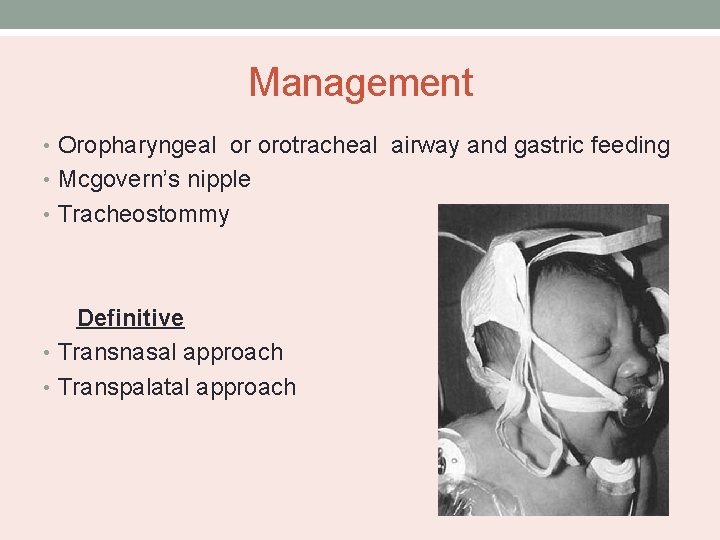

Management • Oropharyngeal or orotracheal airway and gastric feeding • Mcgovern’s nipple • Tracheostommy Definitive • Transnasal approach • Transpalatal approach